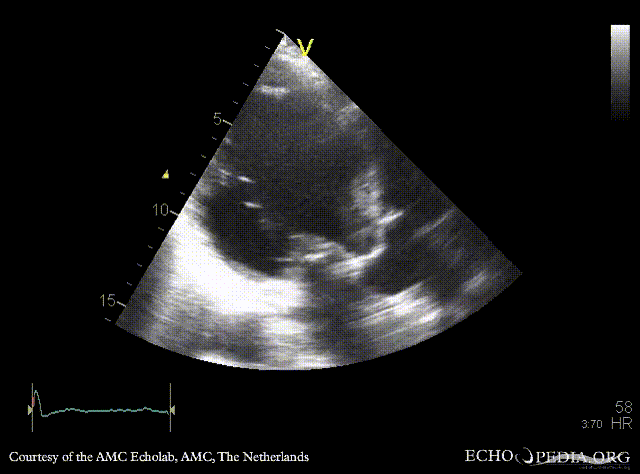

Case 26

Aneurysm of basal inferior wall

Courtesy of: AMC Echolab, AMC, The Netherlands

A2CH: aneurysm of basal inferior wall A3CH: aneurysm of basal inferior wall